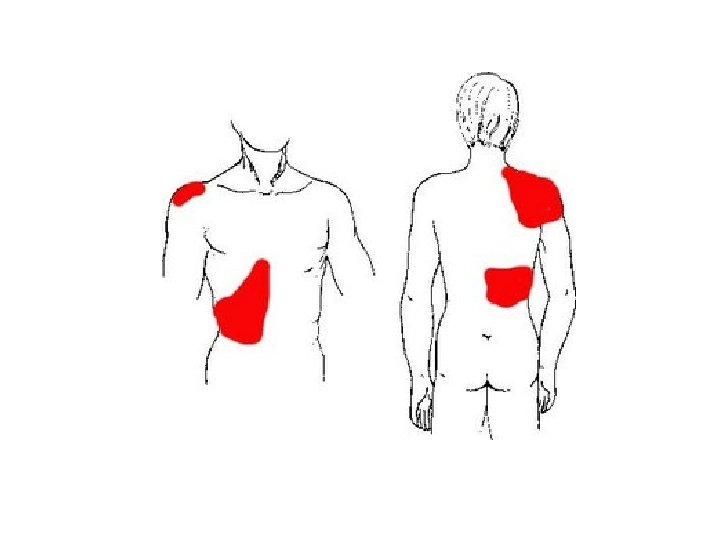

• KLINIKA: - Shenja kryesore eshte dhimbja abdominale e forte qe lokalizohet me veshtiresi nga i semuri. - Dhimbja: fillon ne regionin epigastrik, mund te perhapet edhe ne shpine ose ne shpatullen e djathte, por kryesisht perqendrohet ne kuadrantin superior dexter. - Eshte nje dhimbje me intensitet ne rritje. - Kjo dhimbje pasqyron tensionin dhe inflamacionin e mureve te kolecistes, si pasoje e obstruksionit kalkuloz te duktusit cistik.